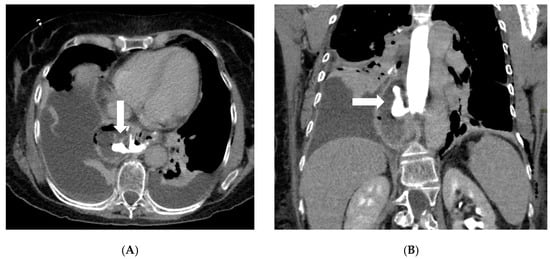

Axial (A) and coronal (B) post-contrast CT scans in a patient on postoperative day 3 following gastric bypass with esophagojejunostomy positioned in the mediastinum (history of sleeve gastrectomy). An esophagojejunal feeding tube is in place. To the right of the esophagojejunal anastomosis, a hypodense collection with internal air components is visible. After oral administration of water-soluble contrast, a posterior dehiscence of the anastomosis is demonstrated, with extraluminal contrast leakage accumulating within the previously described collection (arrows). The copyright of this figure belongs to the authors.

CT’s strengths lie in its high sensitivity for extraluminal gas and fluid, its ability to detect subtle signs like focal mesenteric fat stranding or free air under the diaphragm (which on CT can be discerned even in small volumes), and its capacity to evaluate the entire abdomen for alternative diagnoses. CT can also identify complications like small bowel obstruction from adhesions or hernias, and vascular problems (e.g., splenic infarcts from short gastric artery injury or portal vein thrombosis), which occasionally occur after bariatric surgery [20]. If active bleeding is suspected (for example, a late marginal ulcer hemorrhage or bleeding at a staple line), a CT angiography protocol can be employed to look for contrast extravasation in arterial phase; this can guide interventional radiology if an embolization is needed [36]. One significant strength of CT is in diagnosing internal hernias and small-bowel obstructions, particularly in RYGB patients. An internal hernia occurs when bowel loops protrude through a mesenteric defect created by the surgery (such as the transverse mesocolon defect in a retrocolic Roux limb, the mesenteric gap at the jejunojejunostomy, or Petersen’s space between the Roux limb and transverse colon mesentery) [37]. Classic CT signs of internal hernia after RYGB include a swirled appearance of the mesenteric root fat and vessels (the “whirl” or swirl sign), which reflects the twisting of mesentery as bowel herniates [38] (Figure 3). Other CT hallmarks are clustered, ectopic small-bowel loops (often congregated in an abnormal location such as the left upper quadrant or behind the mesenteric root) with evidence of obstruction (dilated proximal loops and decompressed distal bowel) [39]. Additional reported signs include engorged and stretched mesenteric vessels converging toward the hernia orifice, beaking and crowding of the superior mesenteric vein, the “hurricane eye” sign (a tubular cluster of mesenteric fat surrounded by bowel loops on cross-section), and displacement of the normal jejunojejunal anastomosis position [40]. However, a study by Lockhart et al. and subsequent analyses indicated that mesenteric swirl carries the highest sensitivity and specificity for internal hernia and should be considered pathognomonic in the appropriate clinical context [41]. CT is equally valuable in characterizing fistulous connections and differentiating them from free leaks. For example, a known late complication of RYGB is the formation of a gastro-gastric fistula (GGF), wherein a communication develops between the gastric pouch and the excluded stomach due to staple-line dehiscence. On a CT with oral contrast, a GGF is diagnosed when contrast that was swallowed (entering the pouch) is seen opacifying the excluded stomach, while notably not filling the downstream biliopancreatic limb or duodenum [42].